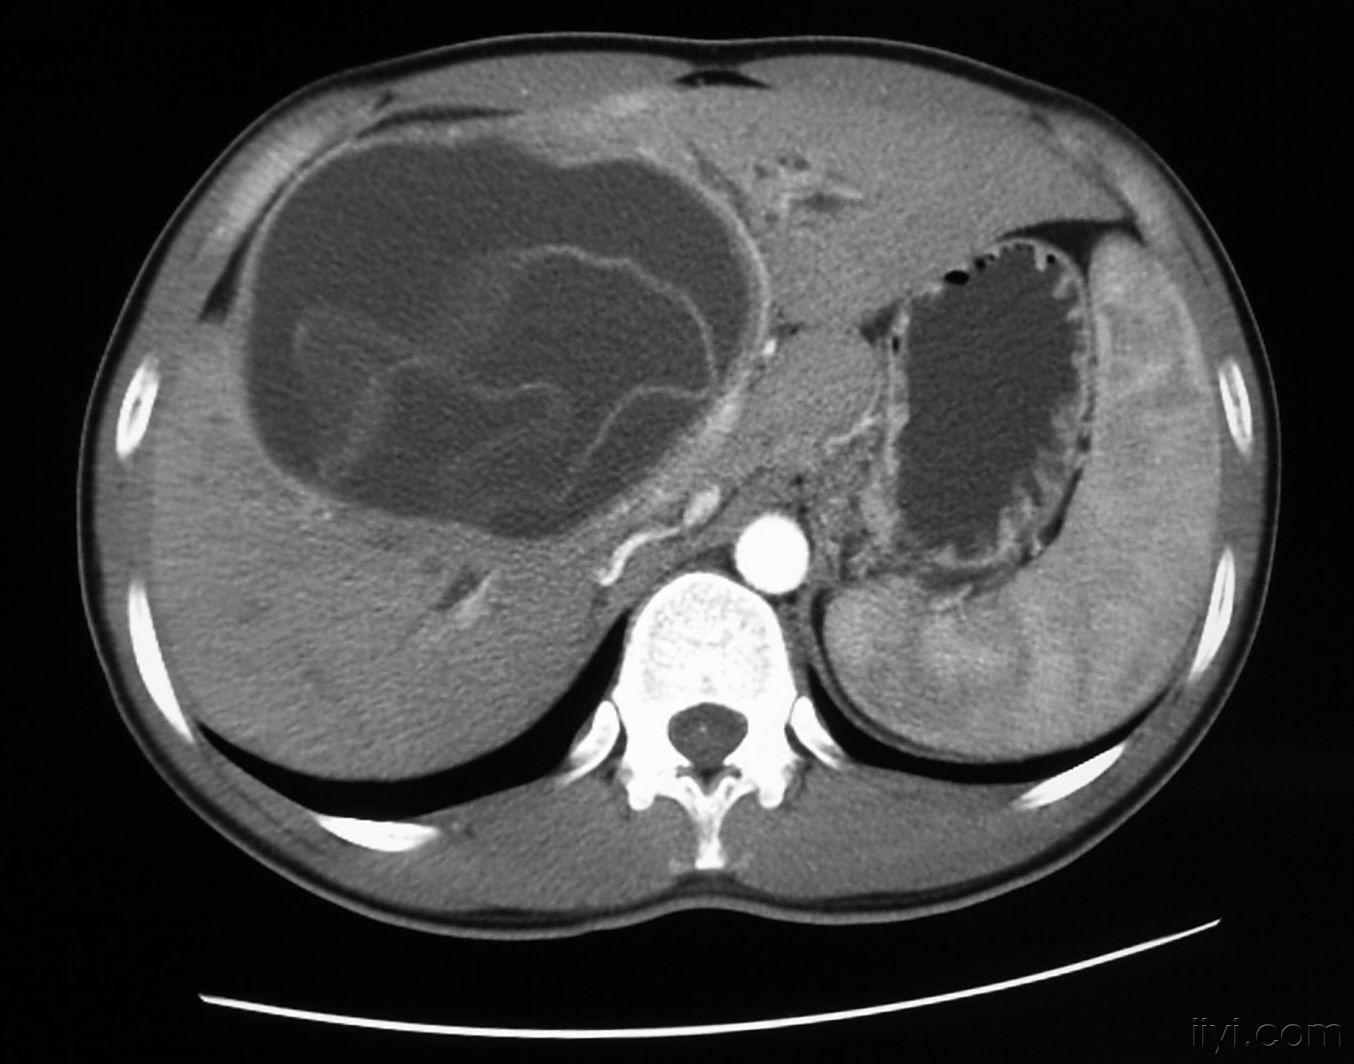

【病例学习】肝包虫病一例ct mr影像表现

病例肝包虫病1例ct及mr影像表现

接上ct三期扫描